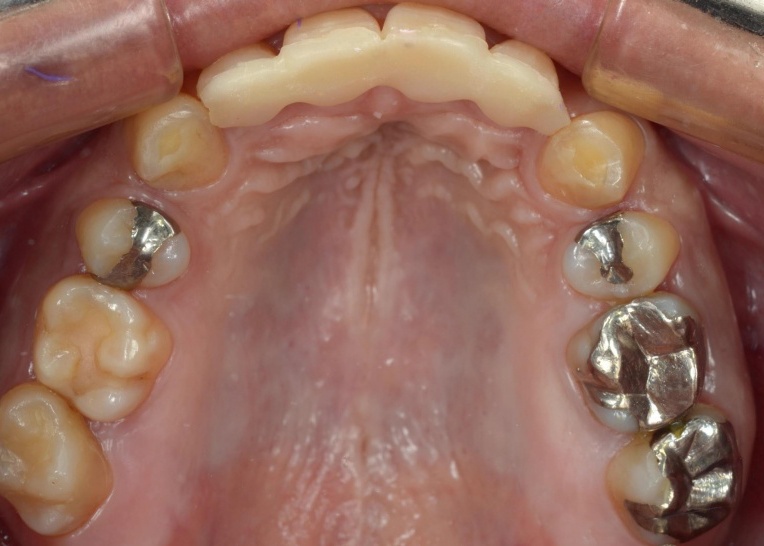

顎の位置が改善し、噛み合わせが安定したことを確認したあと、装着していた仮歯を除去してセラミックの被せ物に置き換えました。

最後に噛み合わせや見た目に問題がないかをしっかりとチェックして、治療を終了しています。